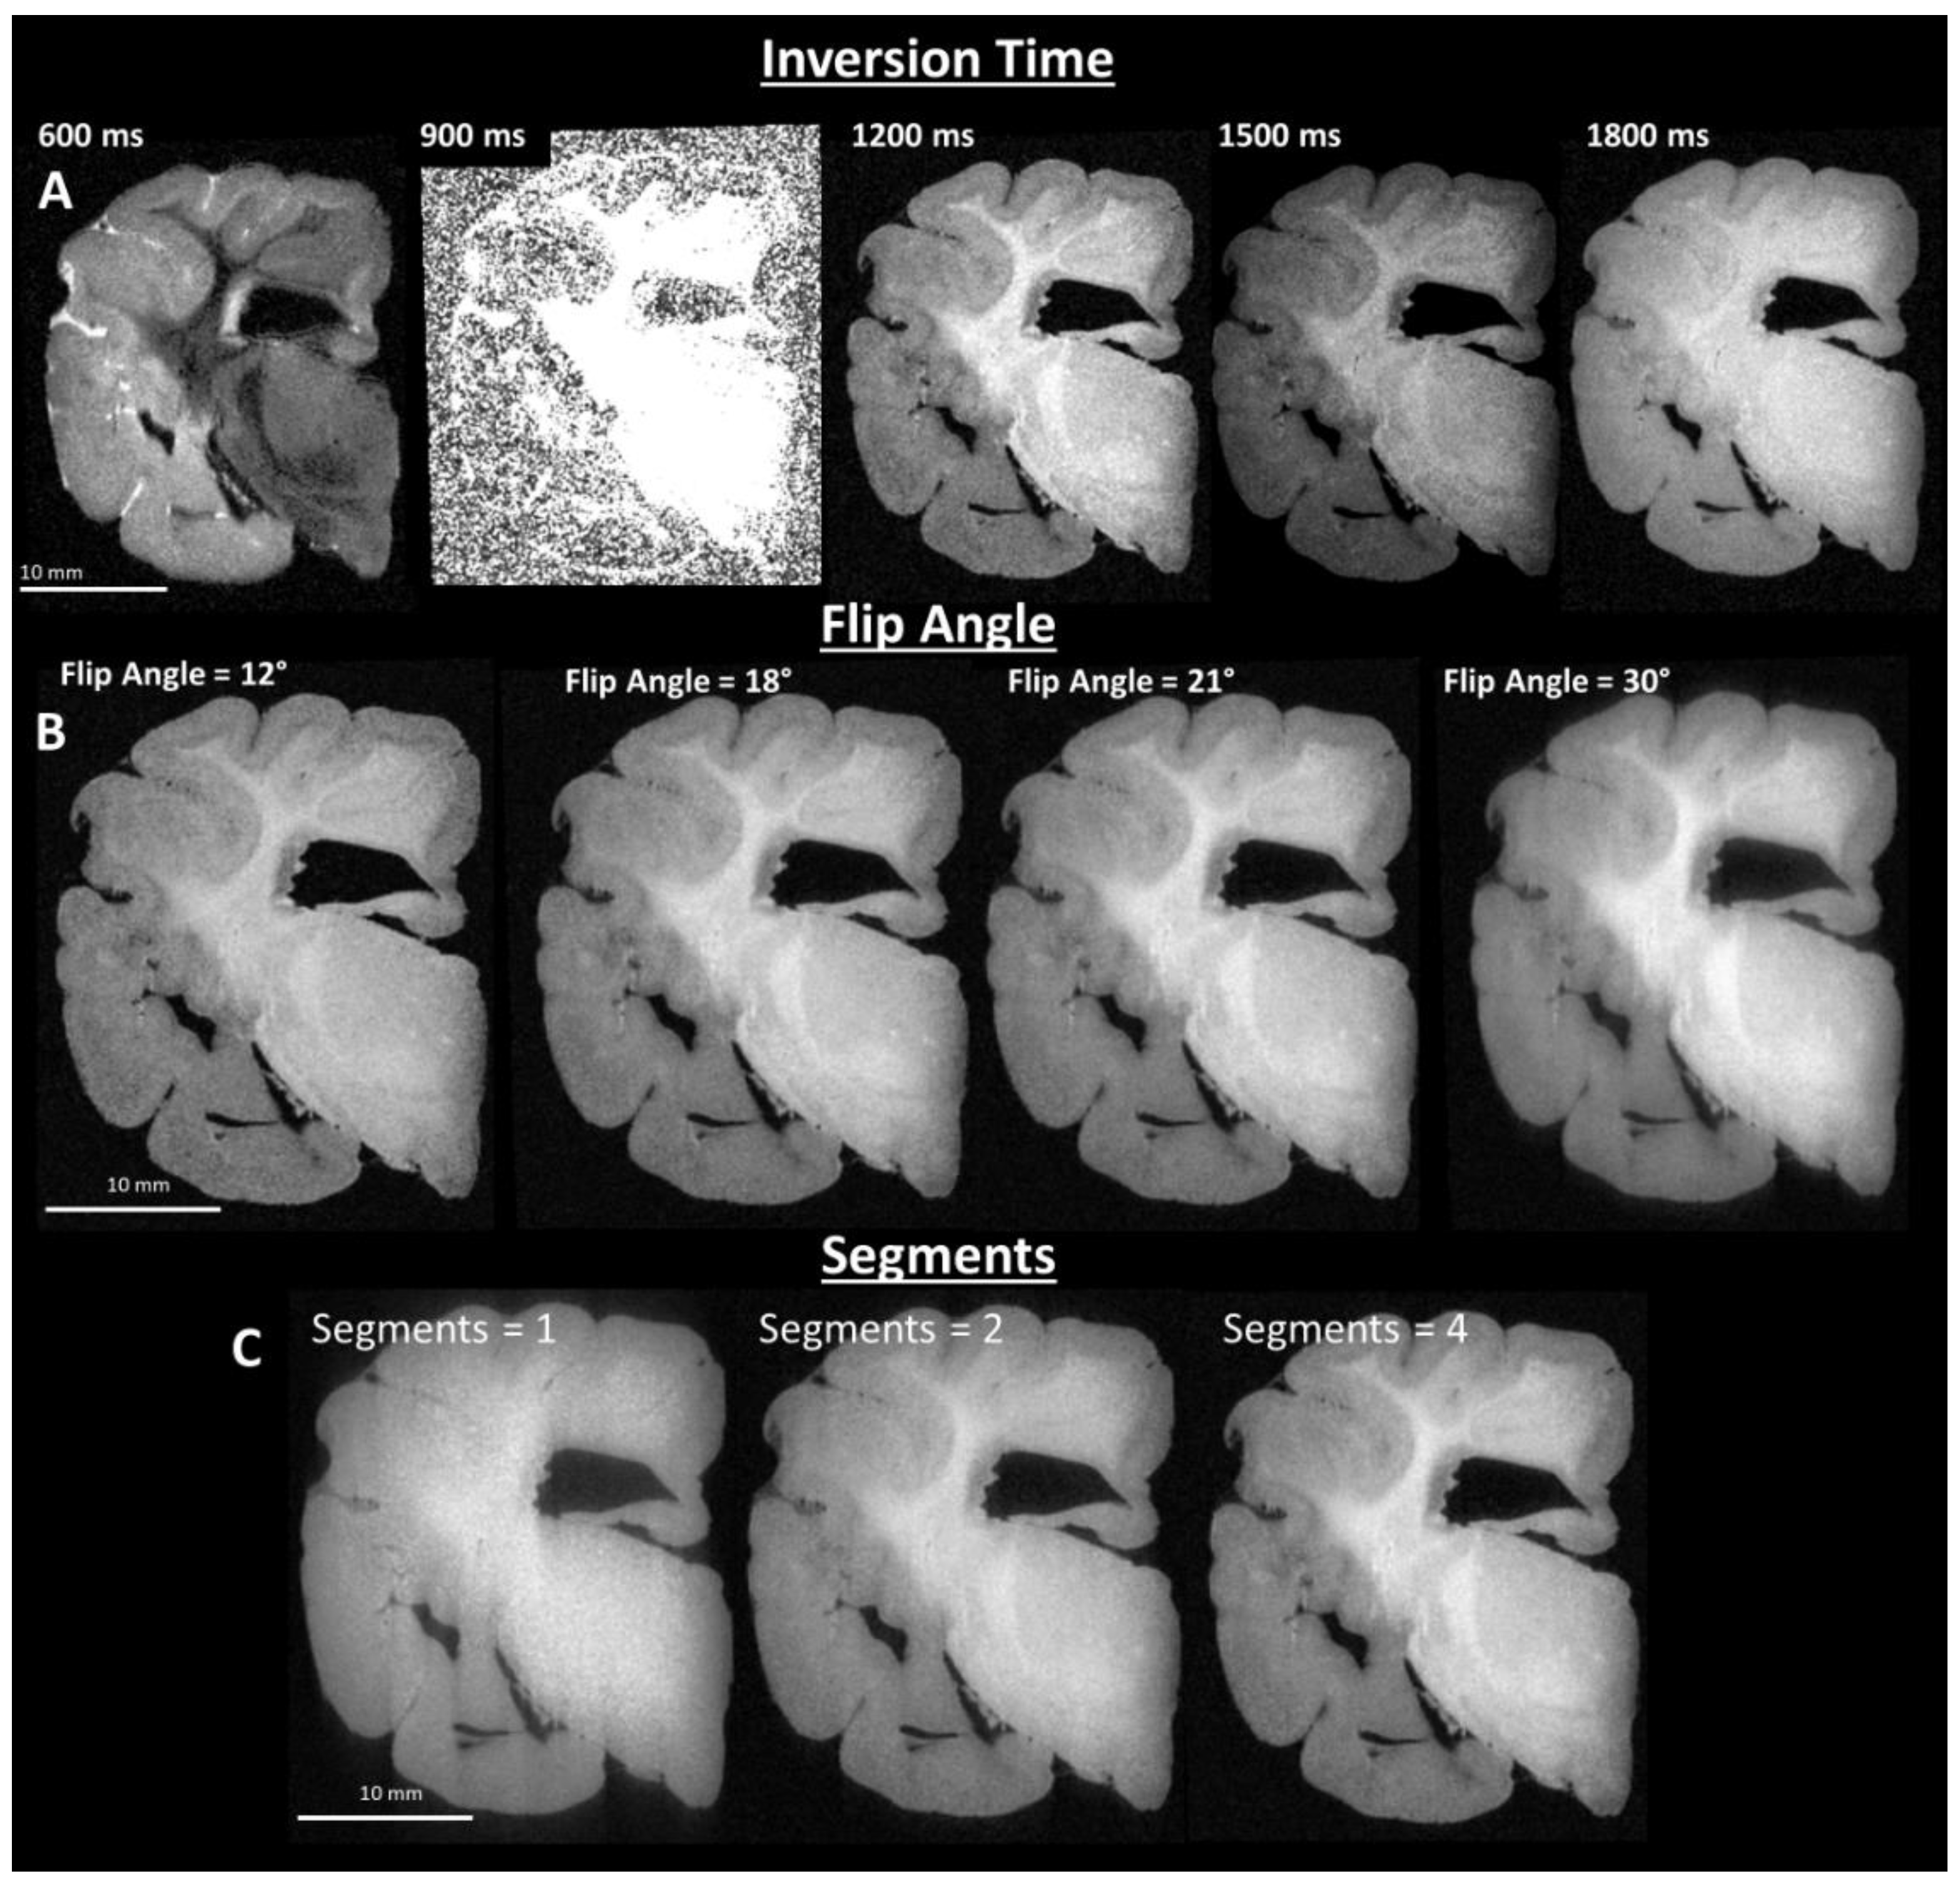

2.3. Image Sequence Development